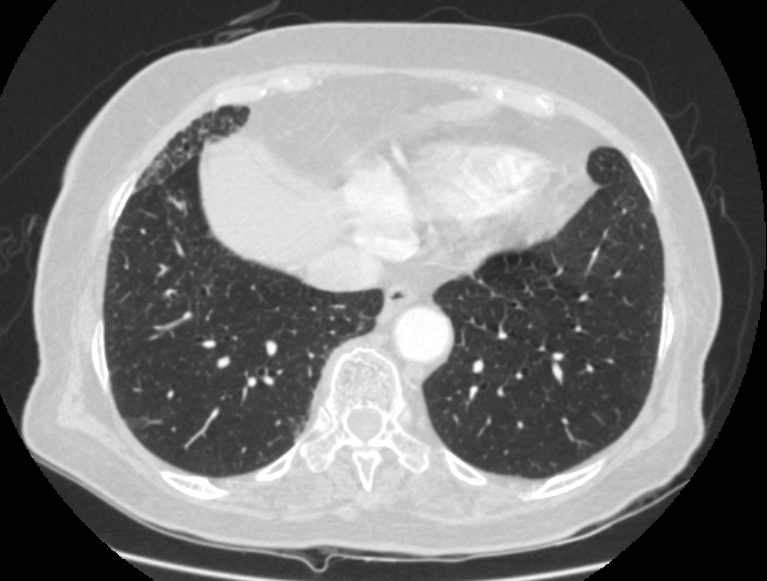

F/73

DM, HTN °ú°Å·Â ÀÖ´Â ºÐÀ¸·Î hip osteoarthritis ·Î THR ½ÃÇà ¿¹Á¤ÇÏ´ø Áß preop CXR abnormality ·Î ÀÇ·ÚµÊ.

never smoker, Á÷¾÷ : ¹«

Cough/Sputum (-/-)

Dyspnea/DOE (-/-)

CBS s rale

wheezing (-)

<³»¿ø½Ã CXR>

< Chest CT >